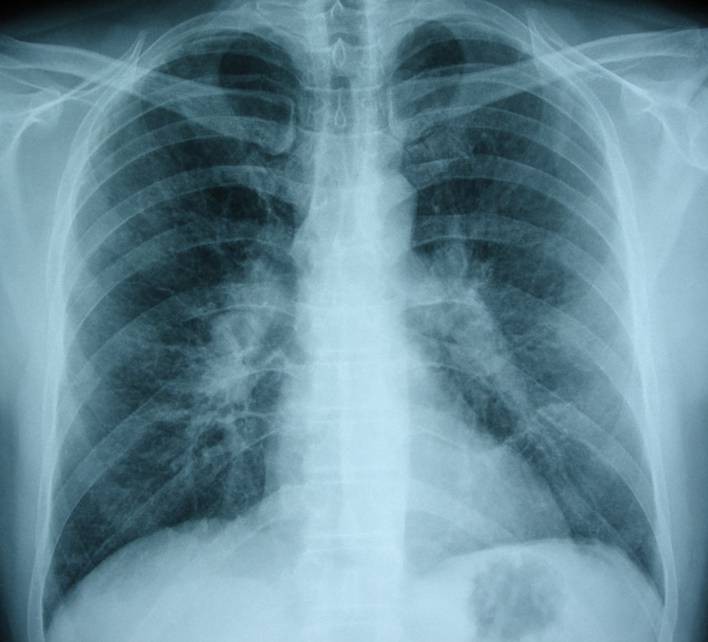

Pneumocystis jiroveci-Pneumonie: AIDS bei HIV-Infektion (oben Thorax pa, unten Thorax-CT) |